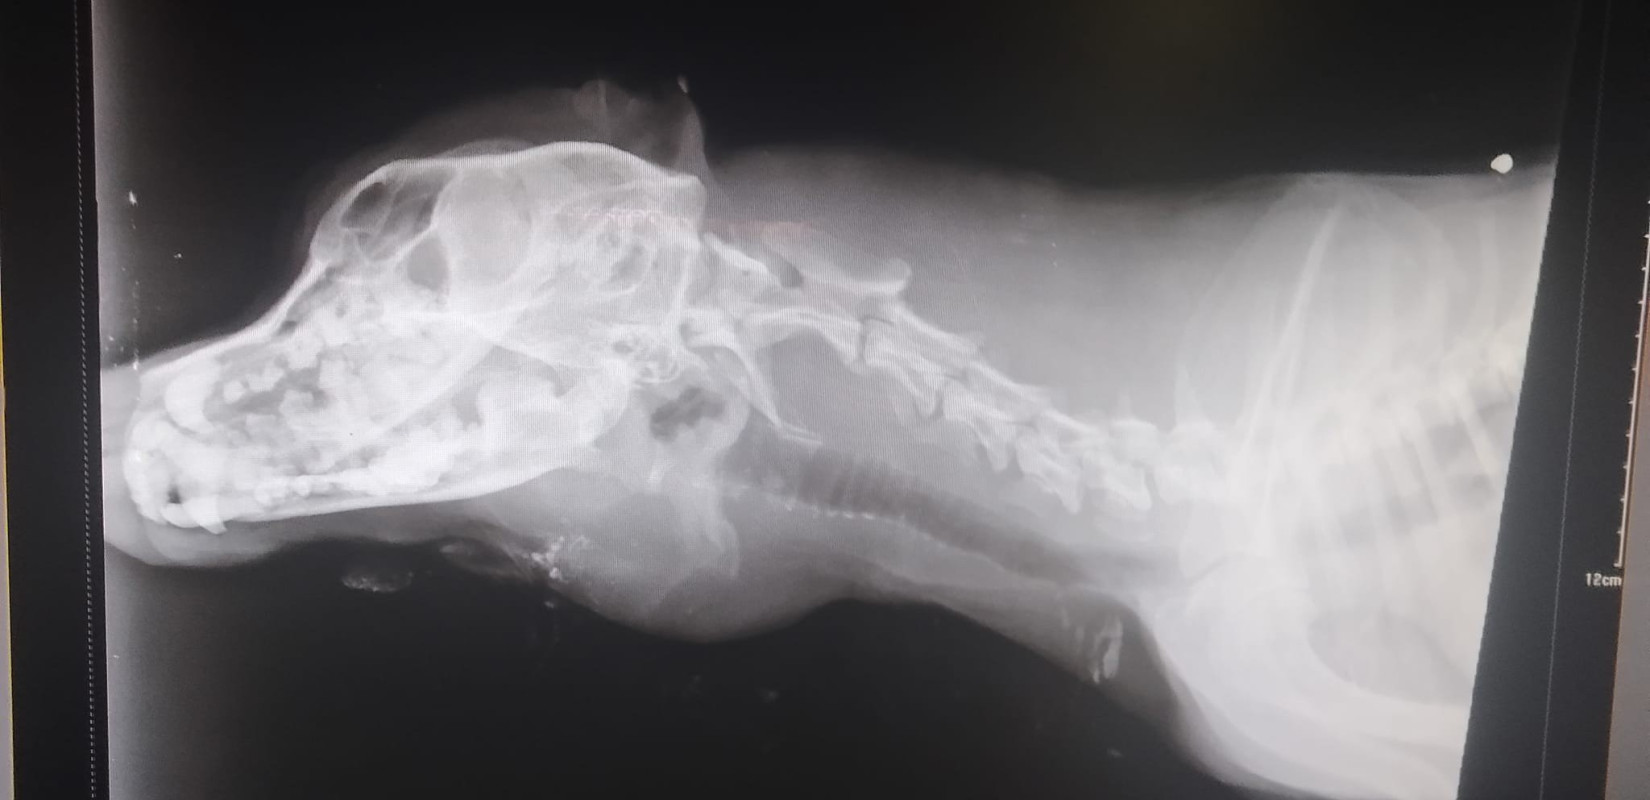

Τα παιδιά ευτυχώς δεν έπαθαν τίποτα ενώ και ο σκύλος γλίτωσε από θαύμα, καθώς έχει τριάντα σκάγια στο κεφάλι

Πρόσθεσέ το στην GoogleΤα παιδιά ευτυχώς δεν έπαθαν τίποτα ενώ και ο σκύλος γλίτωσε από θαύμα, καθώς έχει τριάντα σκάγια στο κεφάλι